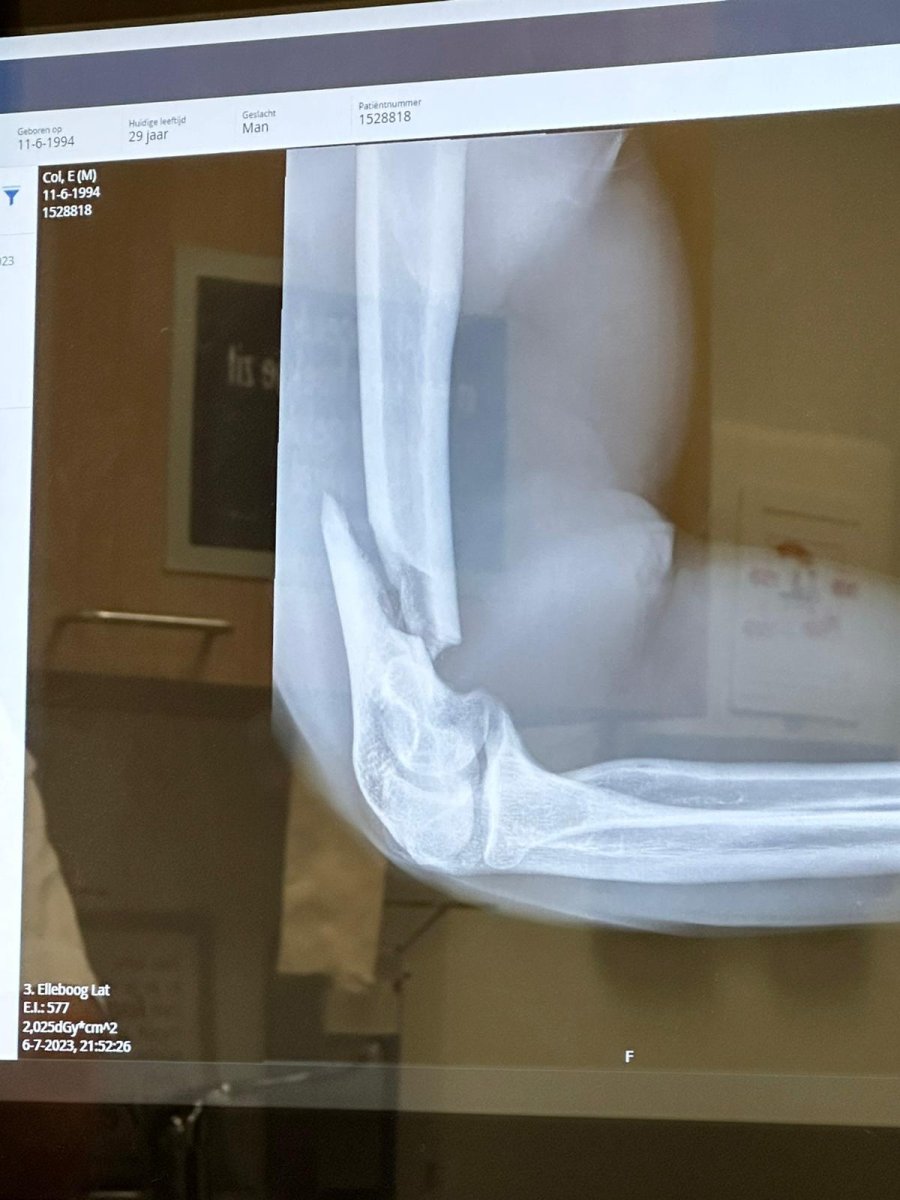

op een zaterdag gevochten in de sportschool (rechter hand gebroken), vervolgens stonden ze maandag aan me deur linker hand gebroken.

Moest in het gips beide handen maar had een vakantie geboekt van paar duizend euro naar Dubai dus niet in het gips laten zetten